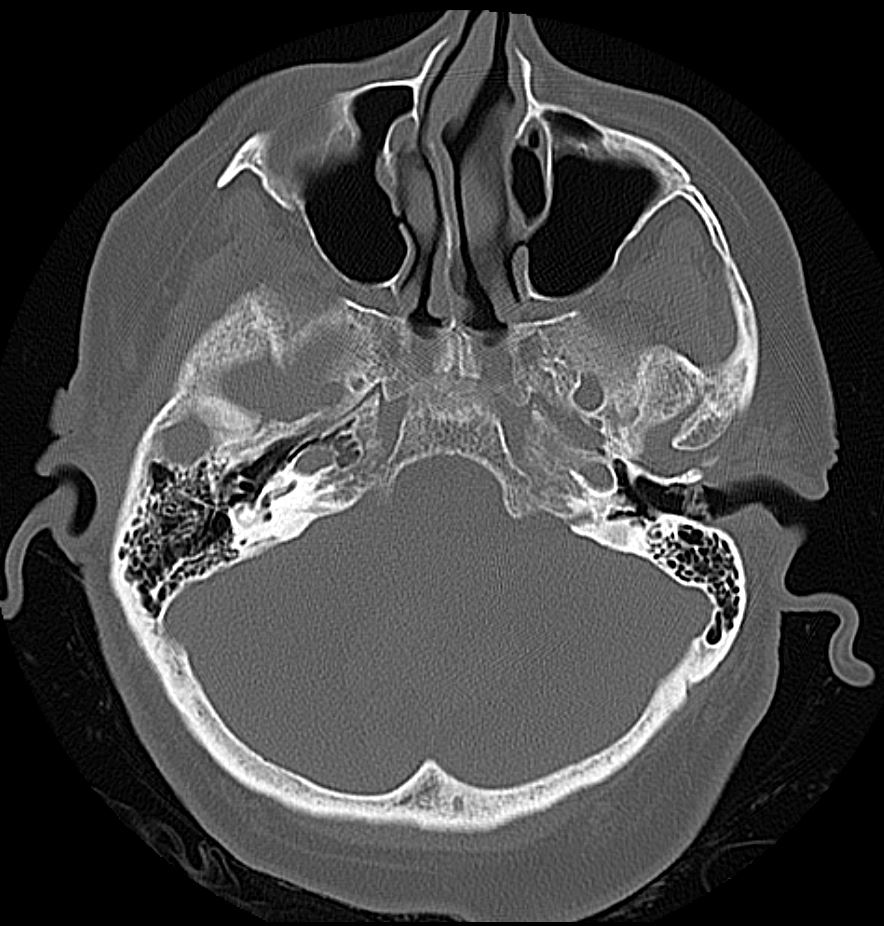

Abbildung

Bildgebung